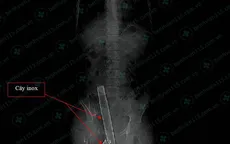

VTV.vn - Bệnh viện Nhân dân 115 (TP.HCM) vừa phẫu thuật thành công cho nam thanh niên 18 tuổi rơi từ tầng trên của căn nhà xuống bị cọc phơi đồ đâm xuyên từ mông vào bụng.